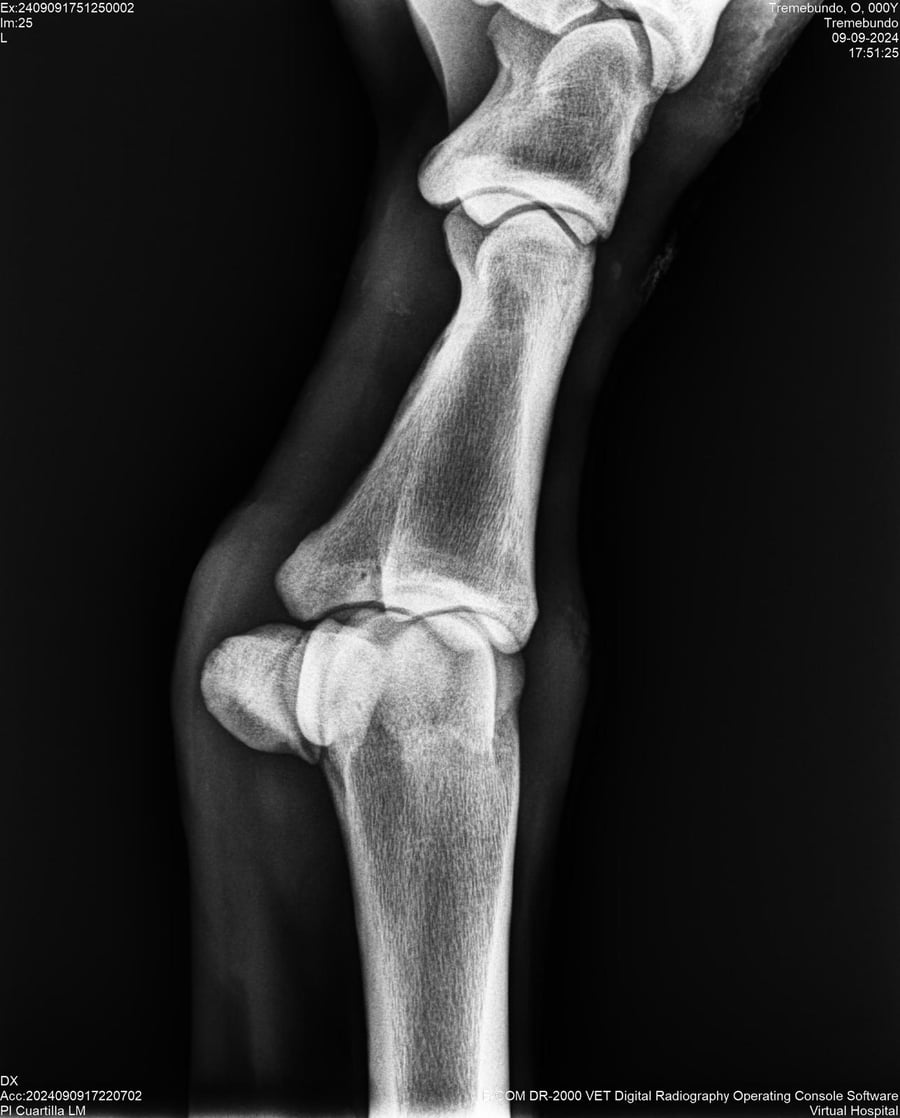

LOTE 37, TREMEBUNDO

Ficha del Lote

Identificador: #291140-

Generacion 2022